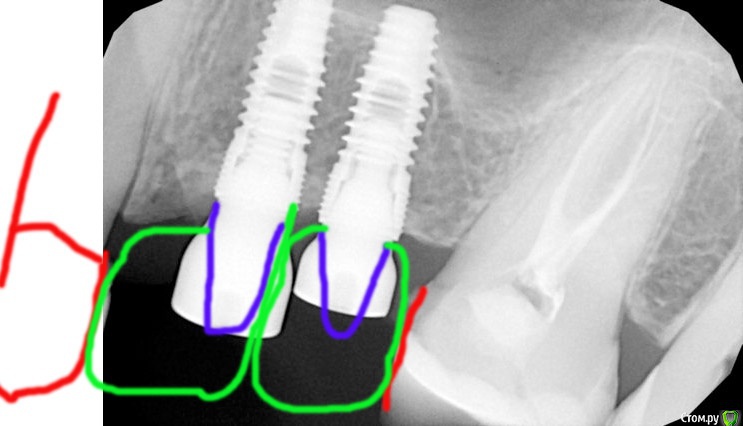

Женька Опубликовано 19 августа, 2020 Поделиться Опубликовано 19 августа, 2020 (изменено) Здравствуйте, коллеги! Подскажите пожалуйста как поступить.Пришла пациентка с установленными имплантатами около 2х лет назад.После установки фдм, хирург отправил к ортопеду в другую клинику (если не ошибаюсь это всё на базе гос. поликлиник было).Придя к ортопеду, пациентке сняли оттиски и "забыли" про неё. Далее история повторилась. После третьего снятия оттиска и отсутствия дальнейших действий пациентка плюнула на это и проходила с фдм до нынешних дней.Имплантаты - Dentium Implantium. Стикеры у пациентки были на руках, да и RVG подтверждает.Если смогу установить трансферы, то как это дело спротезировать лучше?Те фдм, с которыми я сейчас работаю на дентиуме, отличаются от тех что стоят у пациентки, потом вопрос. Смогу ли я стандартной отверткой дентиума открутить фдм?Мне видится вариант замены широкого фдм (если я не ошибся это 5.5) на более узкий, ждём пока мягкие ткани заполнят пустоту (ну или мы им поможем) и соответственно получится установить более узкий трансфер.О сосочке между имплантатами я думаю, можно забыть? ведь расстояние между винтами ~1мм.Также немного беспокоит как сделать будущую коронку 2.4 зуба? Расстояние от имплантата до клыка приличное. Не хотелось бы, чтобы получилась щель между коронкой и зубом. p.s. рвг сделаны с позиционером. Так что размерам на снимке можно худо/бедно доверять Изменено 19 августа, 2020 пользователем Женька Ссылка на комментарий

Jurai Опубликовано 19 августа, 2020 Поделиться Опубликовано 19 августа, 2020 на пятерке формирователь от осстем, отвертка подойдет. На четверке, кажется, тоже подпиленный. Но лучше не беритесь - всем не поможешь, а когда у нее начнет попадать пища между 3 и 4 - окажетесь крайним. Ссылка на комментарий

колесников Опубликовано 19 августа, 2020 Поделиться Опубликовано 19 августа, 2020 Я бы 4ку заглушил,добавил вестибулярно сст,на 5ку поменял фдм пошире и сделал коронку на 5ку с консолью Ссылка на комментарий

Astronaft Опубликовано 20 августа, 2020 Поделиться Опубликовано 20 августа, 2020 Если отбросить вопросы "браться-не браться"... В идеале, перекрутить 4.Ежели обходиться тем чро есть:1. переделать пломбу на клыке -должна быть широкая ровная, что бы был плоскостной контакт, без черного треугольника.2. подровнять 6-ку - плоский медиальны контакт3. абатменты практически без уступа4. цементируемые коронки (овойд в сторону клыка) с давлением на десну. Плоский контакт с клыком. Ну и конечно предупредить что все далеко от идеала. 5 Ссылка на комментарий